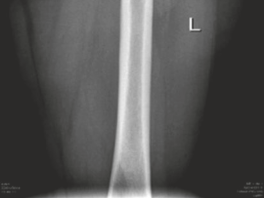

* Femoral Osteochondroplasty (for CAM Lesions):

* The prominent aspect of the femoral head-neck junction (CAM lesion) is resected using osteotomes or high-speed burrs. The goal is to restore the normal offset and sphericity of the femoral head, preventing further impingement.

* The resection should be precisely controlled to avoid over-resection, which can lead to femoral neck fracture, or under-resection, which results in residual impingement. The alpha angle is assessed intraoperatively.